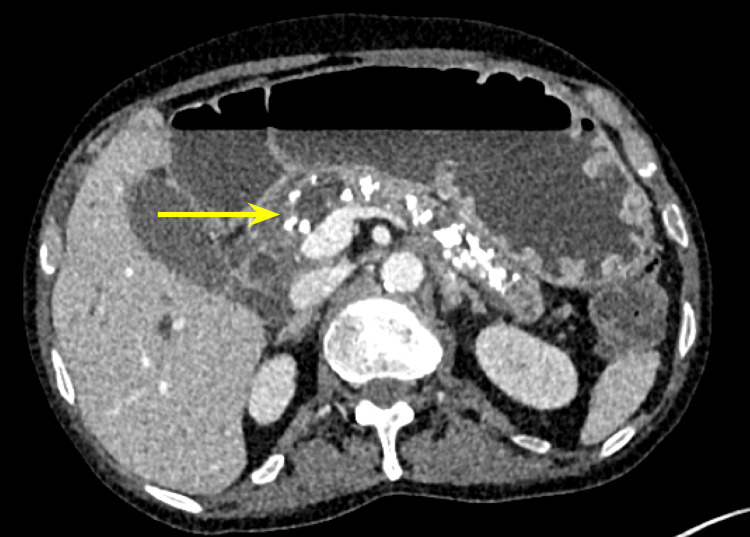

Additionally, there were multiple coarse calcifications throughout the pancreas, consistent with CP (Figure 3). Lastly, the mass was causing significant dilation of the pancreatic (Figure 4), intrahepatic, and extrahepatic biliary ducts.